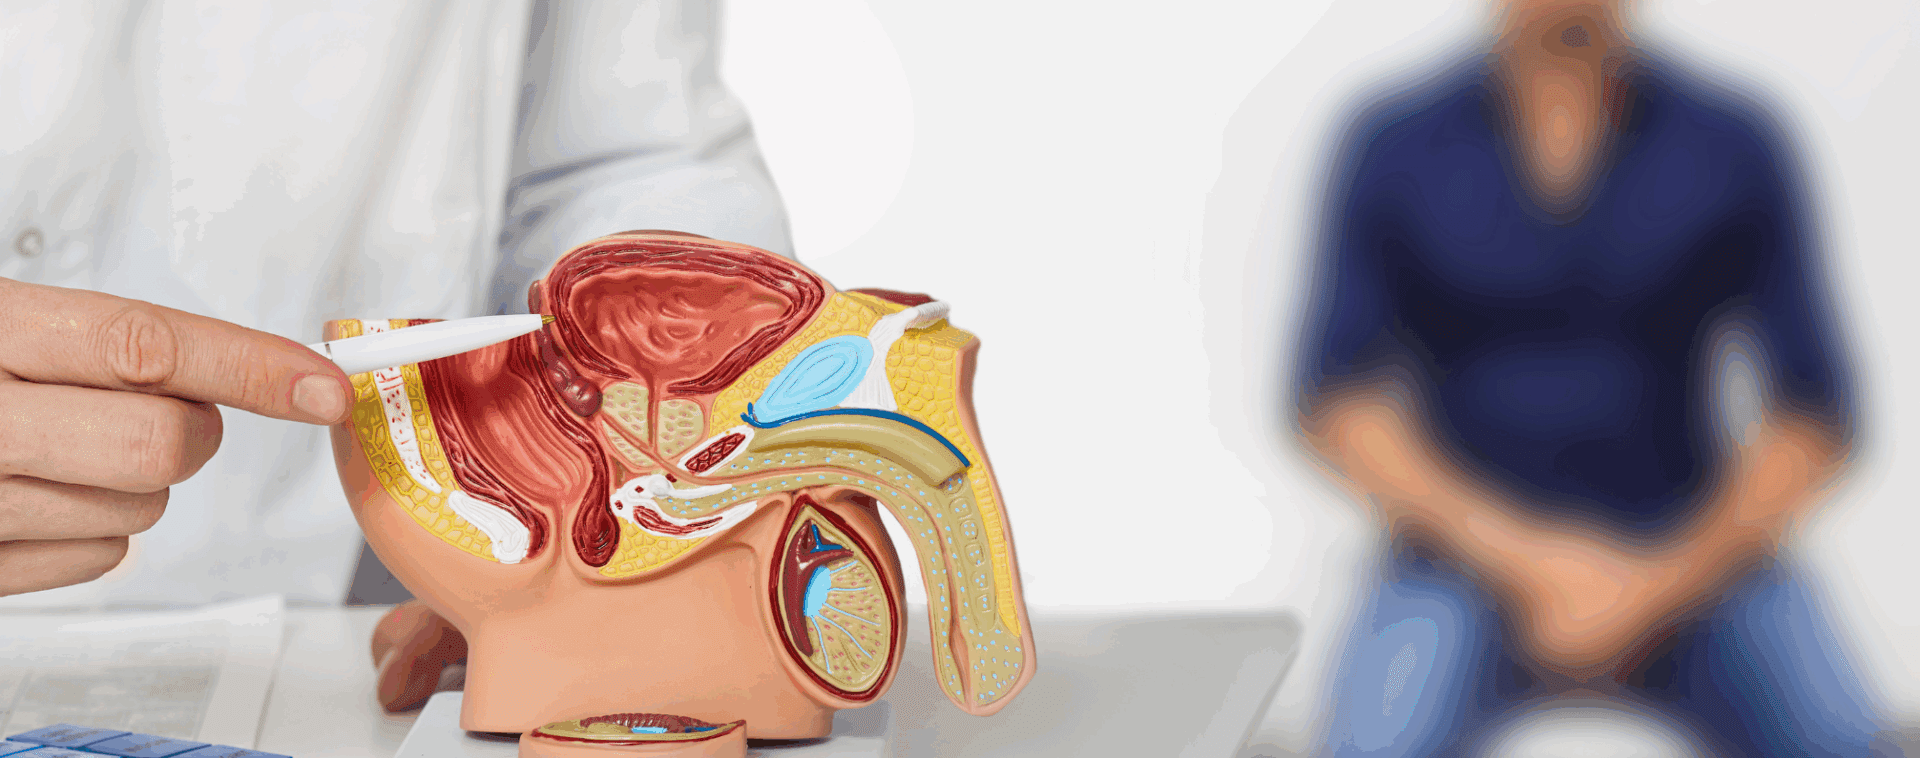

Para entender mejor esta enfermedad y cómo enfrentarla, conversamos con el doctor Felipe Caiceo, coordinador de la especialidad de Urología del Hospital Barros Luco Trudeau.

El cáncer de próstata se desarrolla cuando las células de la glándula prostática comienzan a crecer sin control. Lo complejo es que, en sus primeras etapas, no presenta síntomas evidentes. Con el avance de la enfermedad, pueden aparecer señales como dificultad para orinar, sangre en la orina o el semen, dolor pélvico o disfunción eréctil.

Diagnóstico: más allá de los prejuicios

Detectar el cáncer de próstata a tiempo es posible. Existen herramientas como el Antígeno Prostático Específico (PSA), la resonancia magnética y la biopsia prostática, entre otros exámenes.

Sin embargo, uno de los métodos más conocidos y temidos sigue siendo el tacto rectal. El prejuicio asociado a este examen todavía aleja a muchos hombres de los controles.

El doctor Caiceo comenta: “Es muy común que los pacientes incluso llegan a sentirse ofendidos cuando uno les propone realizar un tacto rectal. Es importante que los pacientes entiendan que no existe el exámen perfecto y por ende uno necesita de la mayor información posible para tomar la mejor decisión. El tacto rectal no tiene costo, es simple, rápido y puede ayudar en muchas situaciones.”